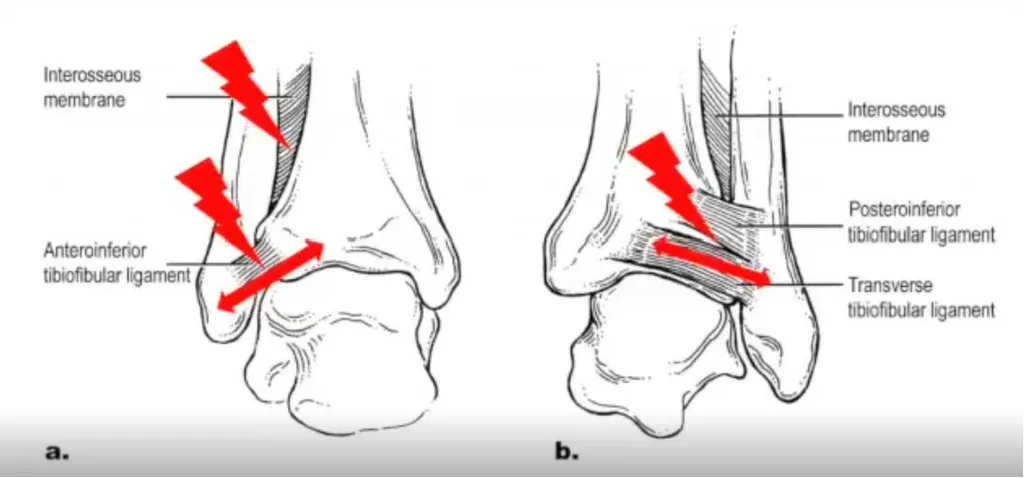

Les traumatismes en rotation sont particulièrement dangereux car la chaussure de ski ne limite pas ce mouvement. Les ligaments entre le tibia et le péroné sont susceptibles d'être rompus, entraînant des douleurs importantes.

Les radiographies initiales peuvent sembler normales, ce qui rend crucial de consulter un chirurgien spécialisé dans la cheville et le pied pour des examens plus approfondis, tels que l'IRM et des radiographies en charge, pour détecter ces blessures ligamentaires.